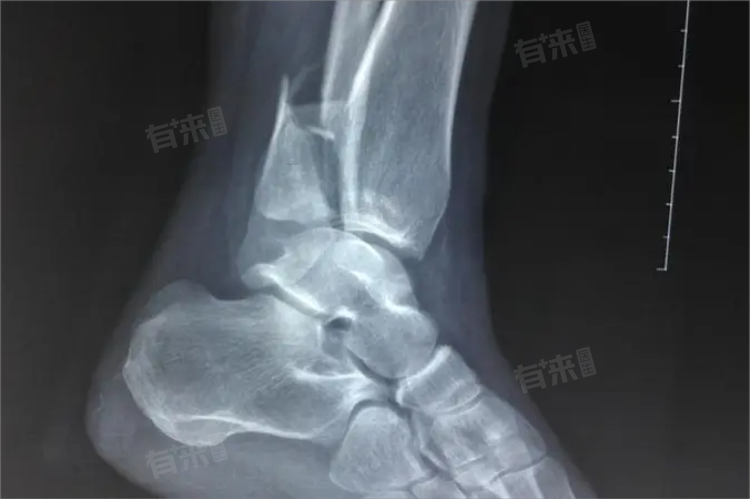

脚踝骨折是指组成踝关节的骨骼,如胫骨远端、腓骨远端、距骨,因直接或间接暴力导致骨的连续性和完整性中断。脚踝骨折会出现疼痛、肿胀、畸形、活动受限、瘀斑等症状。

3、畸形:较严重的脚踝骨折可能导致脚踝部位出现畸形。正常的脚踝外观会发生改变,骨折断端的移位使得骨骼的排列异常,比如脚踝可能会出现内翻或外翻畸形,与另一侧正常脚踝对比差异明显,这是判断骨折较为直观的一个表现。